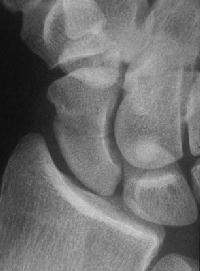

Case 5. Another,same bidirectional technique. Here, I ran the second screw too close to the first, and may have flattened the leading threads - not

ideal. The preop status:

Click for larger image